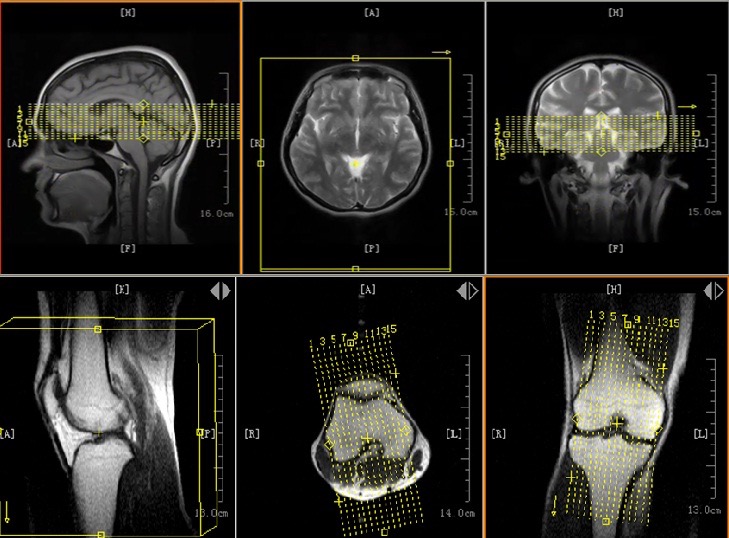

Thần kinh (não, tủy sống, dây thần kinh)

Cơ xương khớp (khớp, chi, cột sống)

Ổ bụng, chậu, niệu – sinh dục

Tim mạch, mạch máu